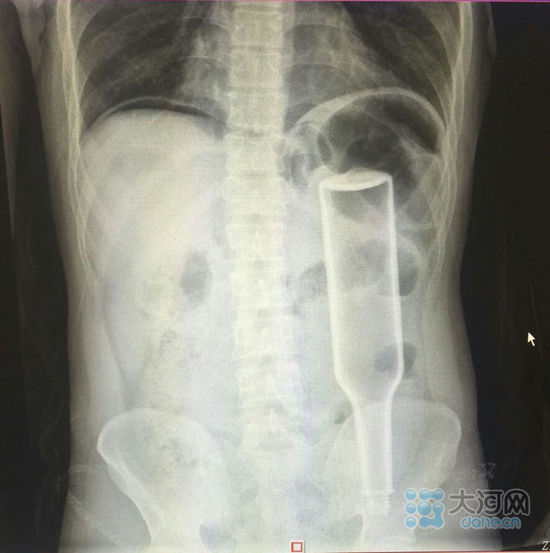

看這片子,花露水瓶子已經很“深入”了。

大河網訊在鄭州務工的外地男子王某,下班到家后閑著沒事兒干,于是將一個長18厘米的花露水瓶子塞進了自己的肛門,不過因為用力過猛,快感沒來,瓶子卻把直腸給戳破了,疼得受不了了,王某羞答答地來到鄭州人民醫院就診,醫生給他做了手術,現在已經出院。